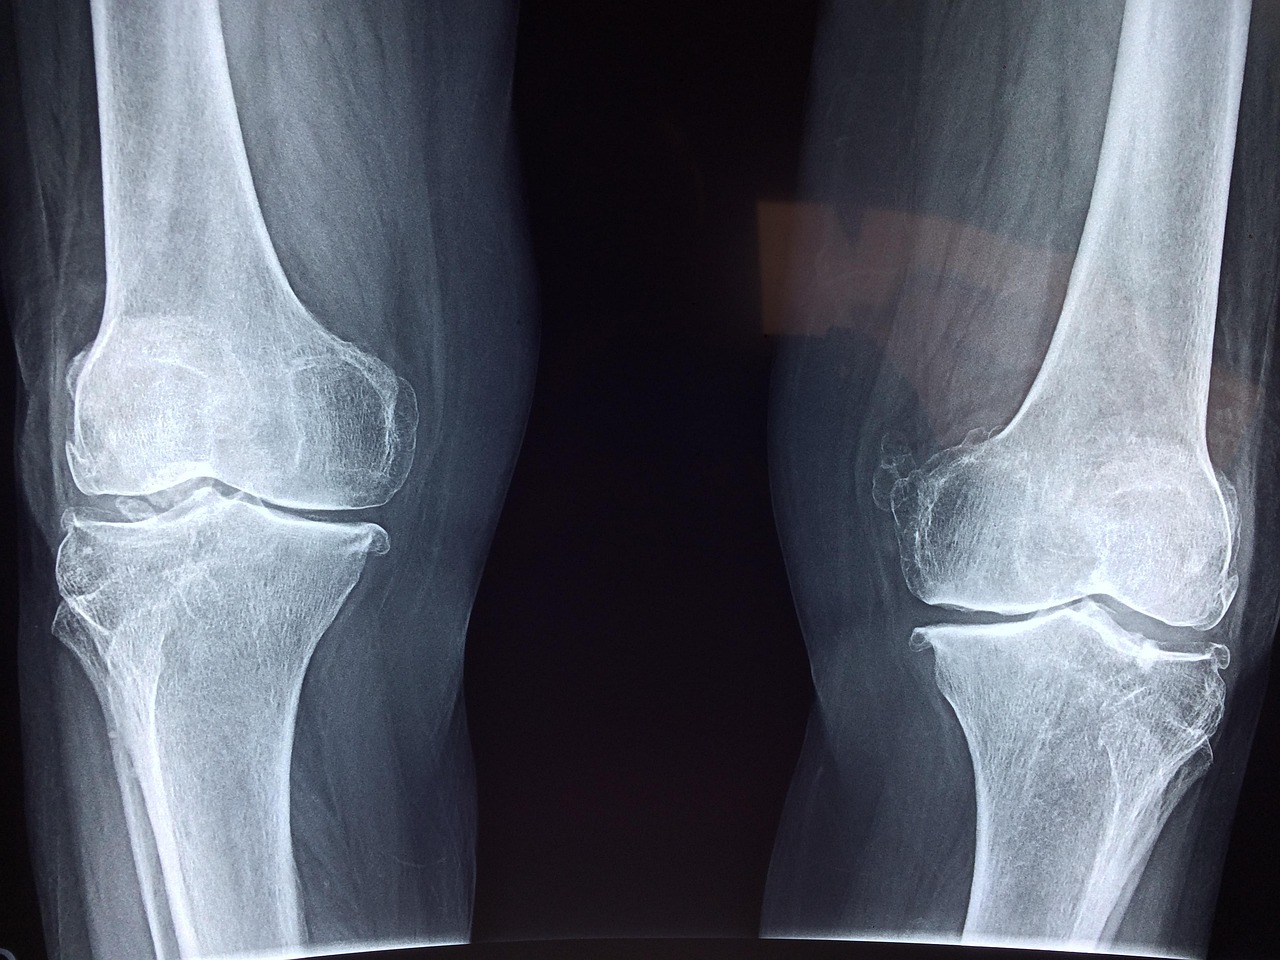

Joint pain is a prevalent issue affecting countless individuals across various age groups. Among the significant causes of joint pain is nutritional deficiencies, including insufficient levels of Vitamin E. This vitamin is crucial for the maintenance of healthy connective tissues and cartilage. Without adequate Vitamin E, the body may struggle to repair tissues effectively, leading to exacerbated joint issues. Research has identified a connection between joint pain and inadequate Vitamin E levels. Individuals experiencing unexplained joint pain should consider having their Vitamin E levels assessed. In some cases, addressing this deficiency through diet or supplementation can yield substantial improvements. Antioxidants like Vitamin E are particularly essential for persons susceptible to joint issues due to wear and tear. By combating oxidative stress, Vitamin E supports the gradual degradation of cartilages. Results may not be immediate, but with consistent supplementation, many people can experience gradual relief over time. In summary, understanding the link between nutrient deficiencies and joint pain is the first step towards developing effective intervention strategies.